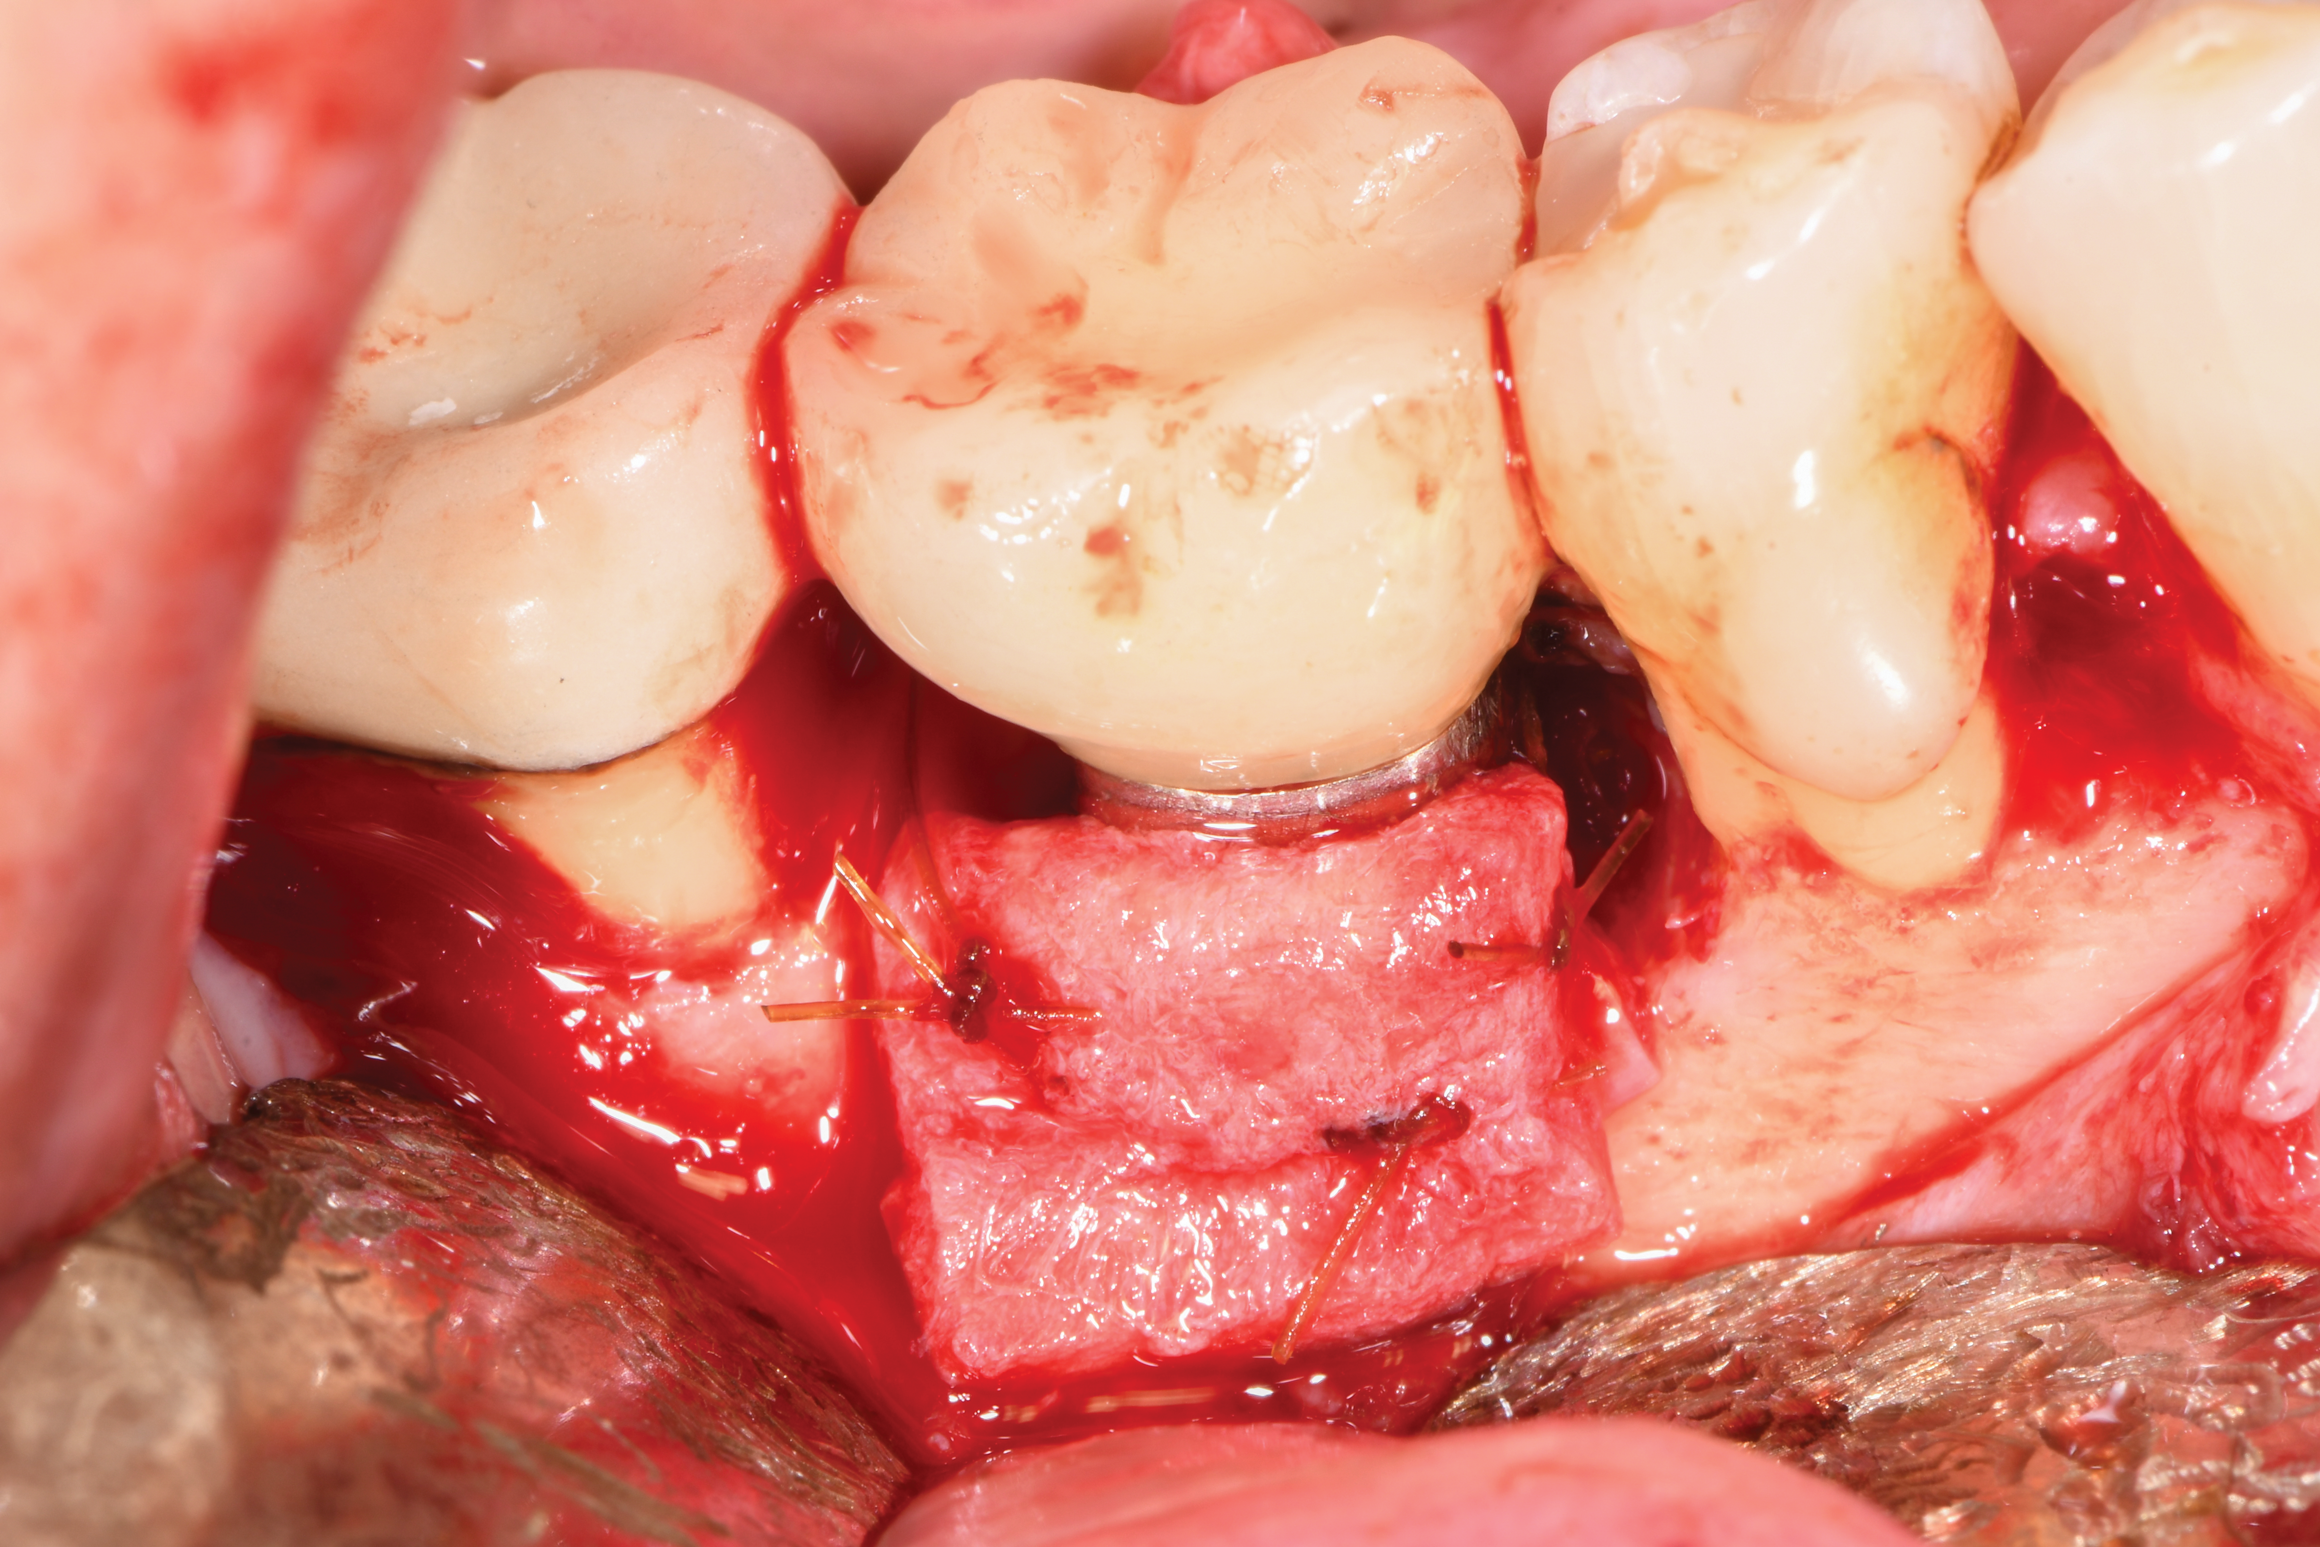

As in the first case, a composite allograft was placed into the defect that contained cryopreserved demineralized freeze-dried bone fibers with cancellous bone chips containing mesenchymal stem cells (Figure 14). This was layered with an amnion-chorion membrane. The flaps were repositioned and secured with 5-0 PTFE sutures using an interrupted technique.

Fig 14. A graft consisting of demineralized freeze-dried fibers and cryopreserved mineralized bone with stem cells was placed at the site. The graft was layered with an amnion-chorion membrane prior to flap closure.

Figure 14